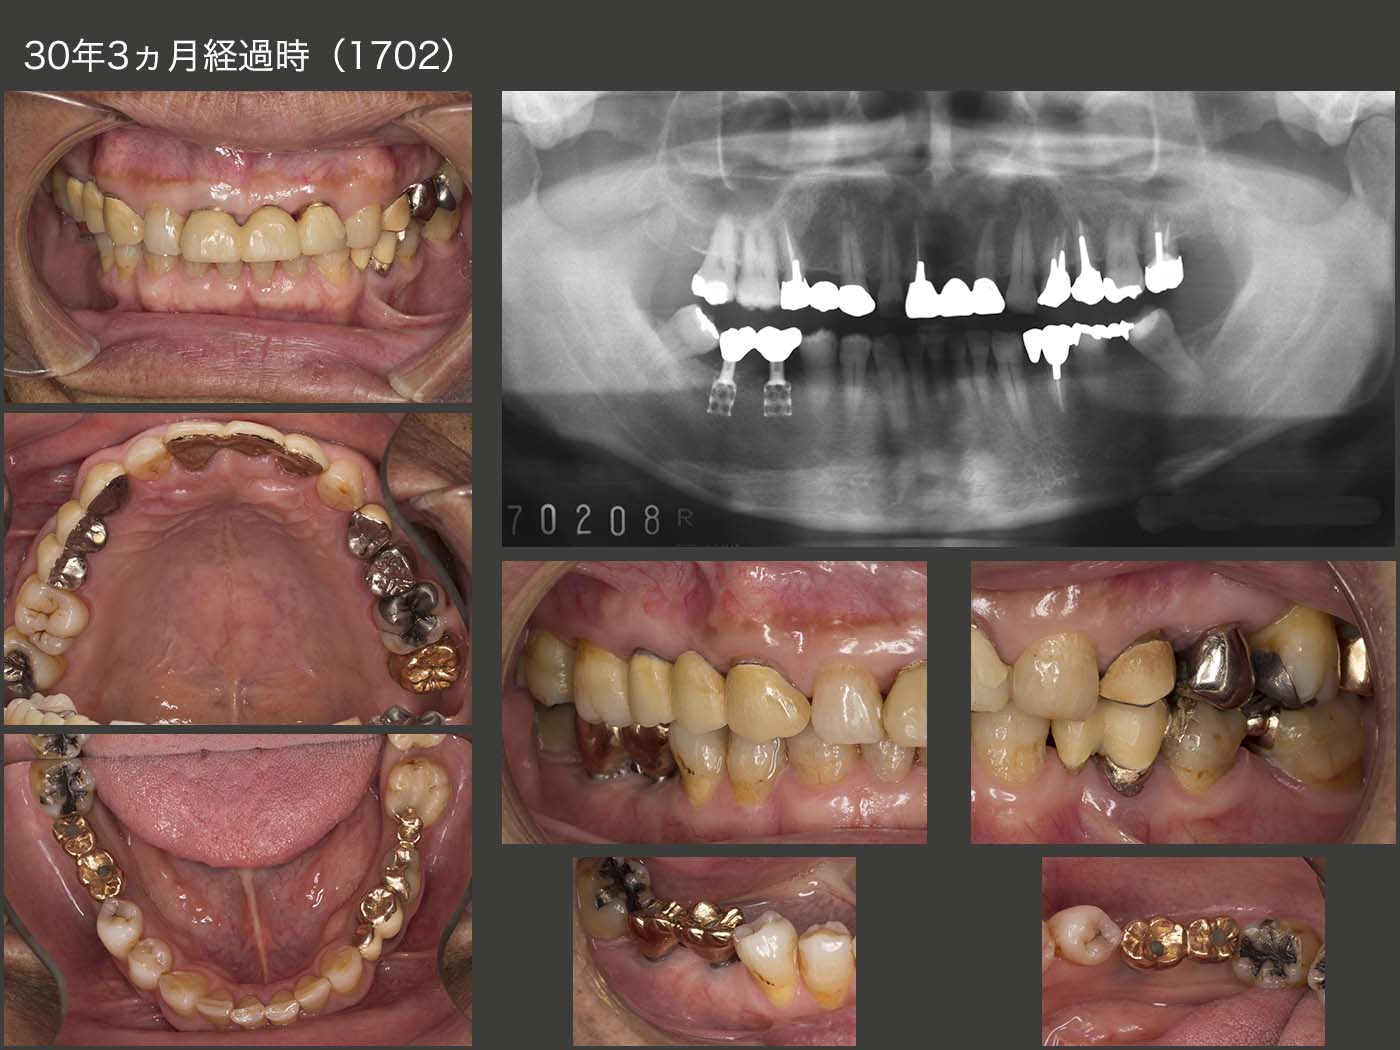

1986年1月初診,31歳男性.当時私は,東京歯科大学病院に勤務しており,その時に担当した患者さん.主訴は右下67の欠損補綴を希望.大学には83年,日本で初めてブローネマルク・インプラントが導入された.歯科医師になって6年目の駆け出しの私としては,ぜひインプラントを用いた治療を行ってみたく,うずうずしていた.丁度同級生にインプラントに詳しい先生がいたので,助手についてもらい,ITIインプラントを植立した.

当時のインプラントはネック部が細く,大きな咬合力には耐えられないと判断し,咬合面をできるだけ小さく製作した.今のインプラントの太さならばもう少し大きく製作できる.しかし小さく製作したことがインプラントに加わる力の軽減に繋がり,インプラントの長期保存に貢献した一つの理由なのかもしれない.

1997年まで,大学病院で定期健診を行っていた.その後暫く拝見することができなかったが,2008年以降,私の診療室まで何時間もかけて通院してくださるようになった.右下のインプラントは30年経過しても順調だが,この理由は2つあると考えている.まず,先にも述べたが咬合面の面積を小さく製作したことが挙げられる.つぎに,インプラントでは嚙んだ時の食感が少ないことから,上下顎に歯のある左側で主に咀嚼していたからと考えている.しかし患者さんは,右側でも咬んでいるとおっしゃっているし,左側の歯に特に問題が生じていないことから,確かに両側で咬んでいるのかもしれない.